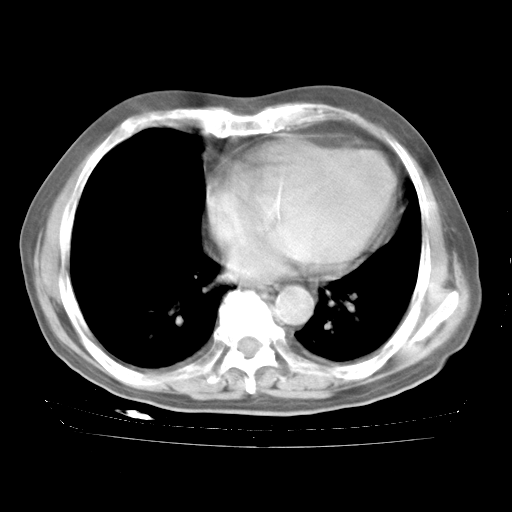

4月28日肺部CT